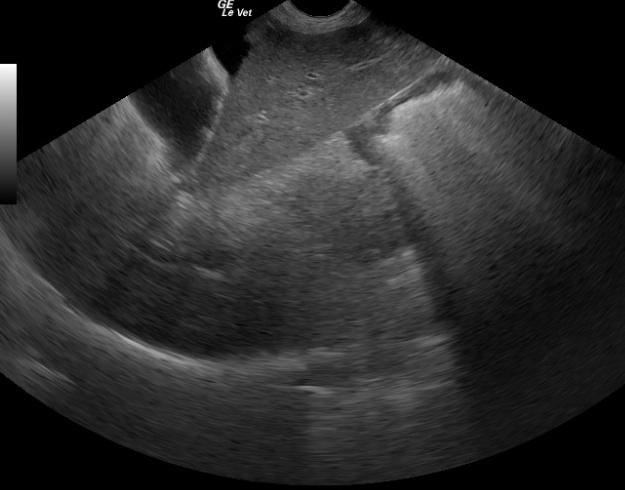

A 9-year-old MN English Pointer was presented for decreased appetite, weight loss, lethargy, and halitosis. Physical examination findings were generalized muscle wasting and slightly pale mucous membranes. The only abnormality on urinalysis was trace proteinuria; UPC showed borderline proteinuria. Abnormalities on CBC were anemia and thrombocytopenia. The patient was treated with Prednisone pending an ultrasound.